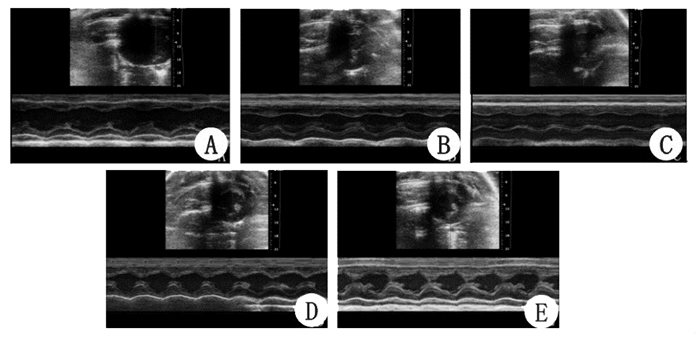

图 2表 1所示,ROSC 4 h时sevo组和control组舒张期左室后壁厚度(left ventricular posterior wall diameter,LVPWd)较sham组增厚,sevo组和control组心输出量(cardiac output,CO)较sham组下降,差异有统计学意义(P<0.05)。而sevo组舒张期左室后壁增厚程度小于control组,sevo组心输出量高于control组,差异有统计学意义(P<0.05)。ROSC 24 h时仅control组在左室后壁厚度、心输出量方面明显差于sham组(P<0.05)。各组动物左室射血分数(ejection fraction,EF)在ROSC 4 h、24 h比较差异无统计学意义(P>0.05)。

A:sham组;B:sevo组4 h;C:control组4 h;D:sevo组24 h;E:sevo组24 h 图 2 各组心脏超声图片 Fig 2 The echocardiography of each group

心脏彩超示心肺复苏后LVPWd增厚、心输出量下降,sevo组LVPWd增厚程度较control组明显减轻,心输出量明显高于control组,说明七氟醚可以减轻复苏后心功能不全。分析复苏后室壁增厚的原因可能是心肌水肿、缺血挛缩。当心脏停止收缩后,心肌淋巴回流停止,微血管通透性增加,血浆渗出而无淋巴回流导致液体积聚于心肌间隙,形成心肌水肿。缺血-再灌注后,机体产生大量氧自由基、心肌细胞钙超载,加重心肌细胞、血管内皮损伤,使心肌水肿更加明显[10]。而钙超载也会导致心脏缺血挛缩,室壁僵硬,降低心肌顺应性[11]。心肌水肿、缺血挛缩导致左室壁进行性增厚、心室容量明显减少,降低心输出量[12]。有文献报道,心脏骤停ROSC后患者,血流动力学不稳定、低心排出量主要发生在复苏后4~7 h内,在复苏后24 h左右,患者心功能会不同程度的恢复[13]。笔者发现ROSC后24 h,sevo组与control组室壁增厚、低心排出量均得到不同程度的改善,但control组较sham组仍差别显著。